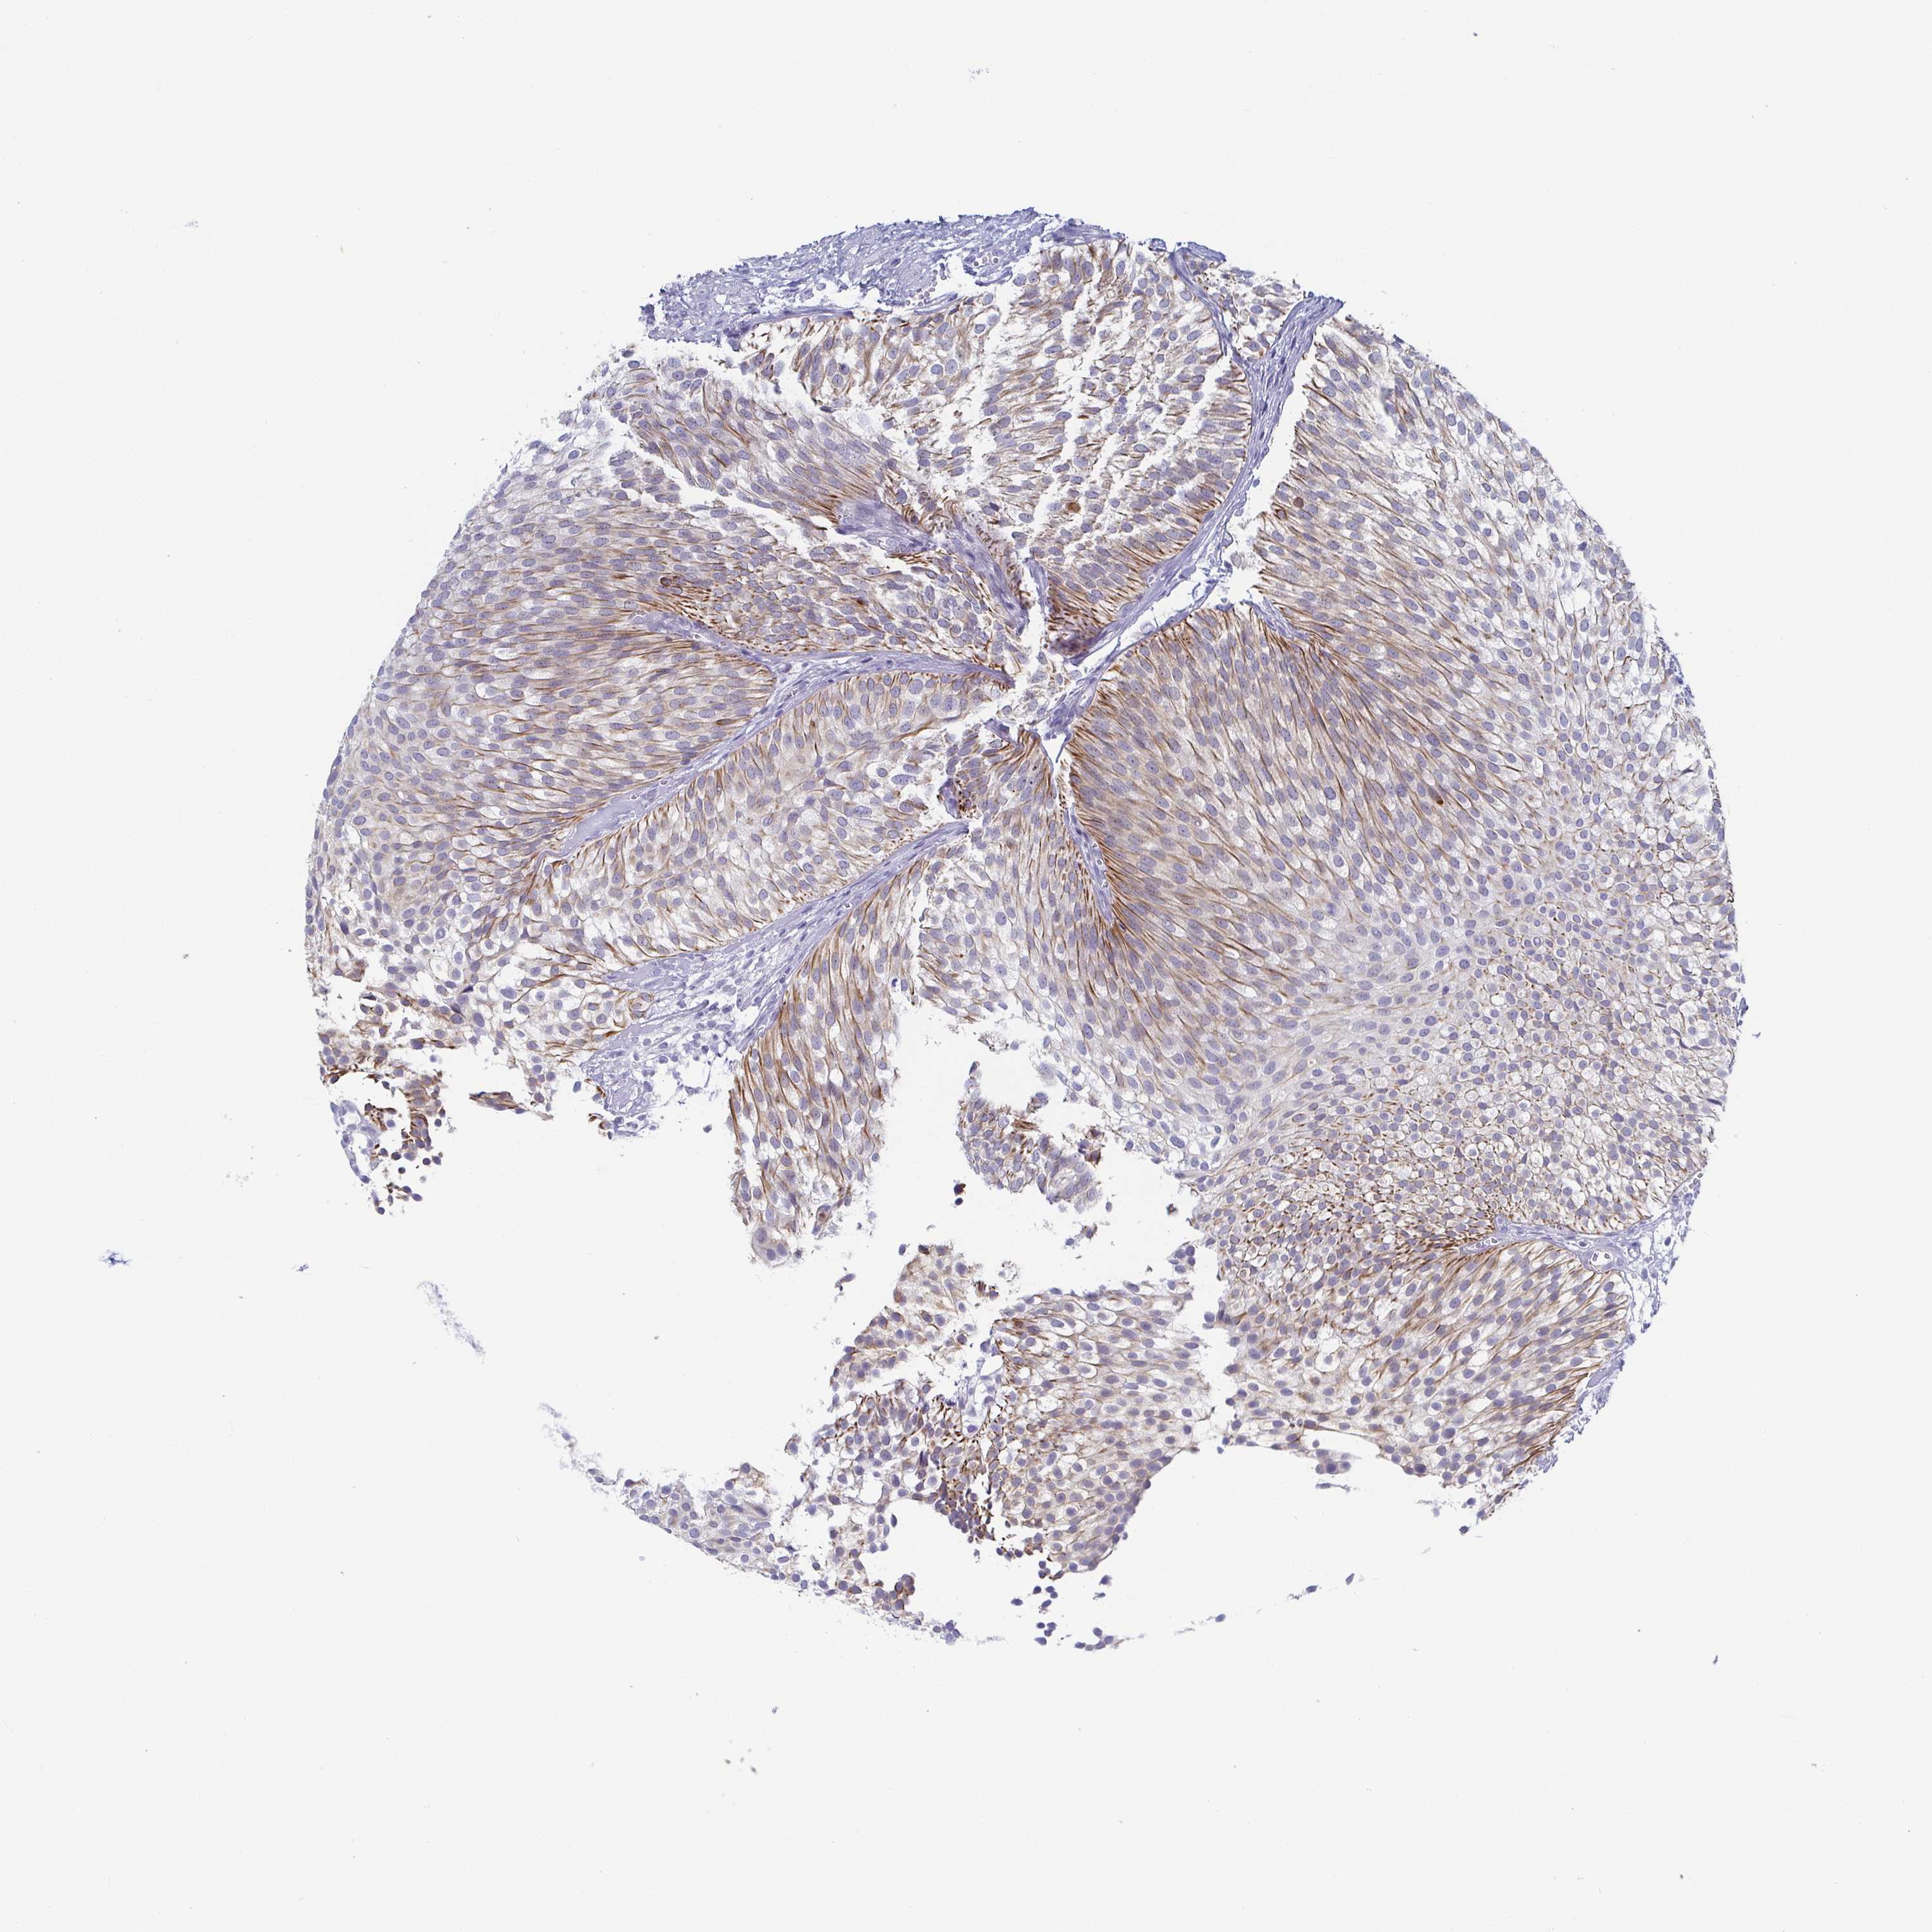

UROTHELIAL CANCER - Protein expressioni

A mouse-over function shows sample information and annotation data. Click on an image to view it in a full screen mode. Samples can be filtered based on level of antibody staining by selecting one or several of the following categories: high, medium, low and not detected. The assay and annotation is described here.

Note that samples used for immunohistochemistry by the Human Protein Atlas do not correspond to samples in the TCGA dataset.

Antibody stainingi

Antibody staining in the annotated cell types in the current human tissue is reported as not detected, low, medium, or high, based on conventional immunohistochemistry profiling in selected tissues. This score is based on the combination of the staining intensity and fraction of stained cells.

Each image is clickable and will lead to virtual microscopy that enables deeper exploration of all samples and also displays staining intensity scores, fraction scores and subcellular localization as well as patient and tissue information for each sample.

Antibody HPA053343

Staining

High

Medium

Low

Not detected

Intensity

Strong

Moderate

Weak

Negative

Quantity

>75%

75%-25%

<25%

None

Location

Nuclear

Cytoplasmic/membranous

Cytoplasmic/membranous,nuclear

Urothelial carcinoma, High grade

Urothelial carcinoma, Low grade